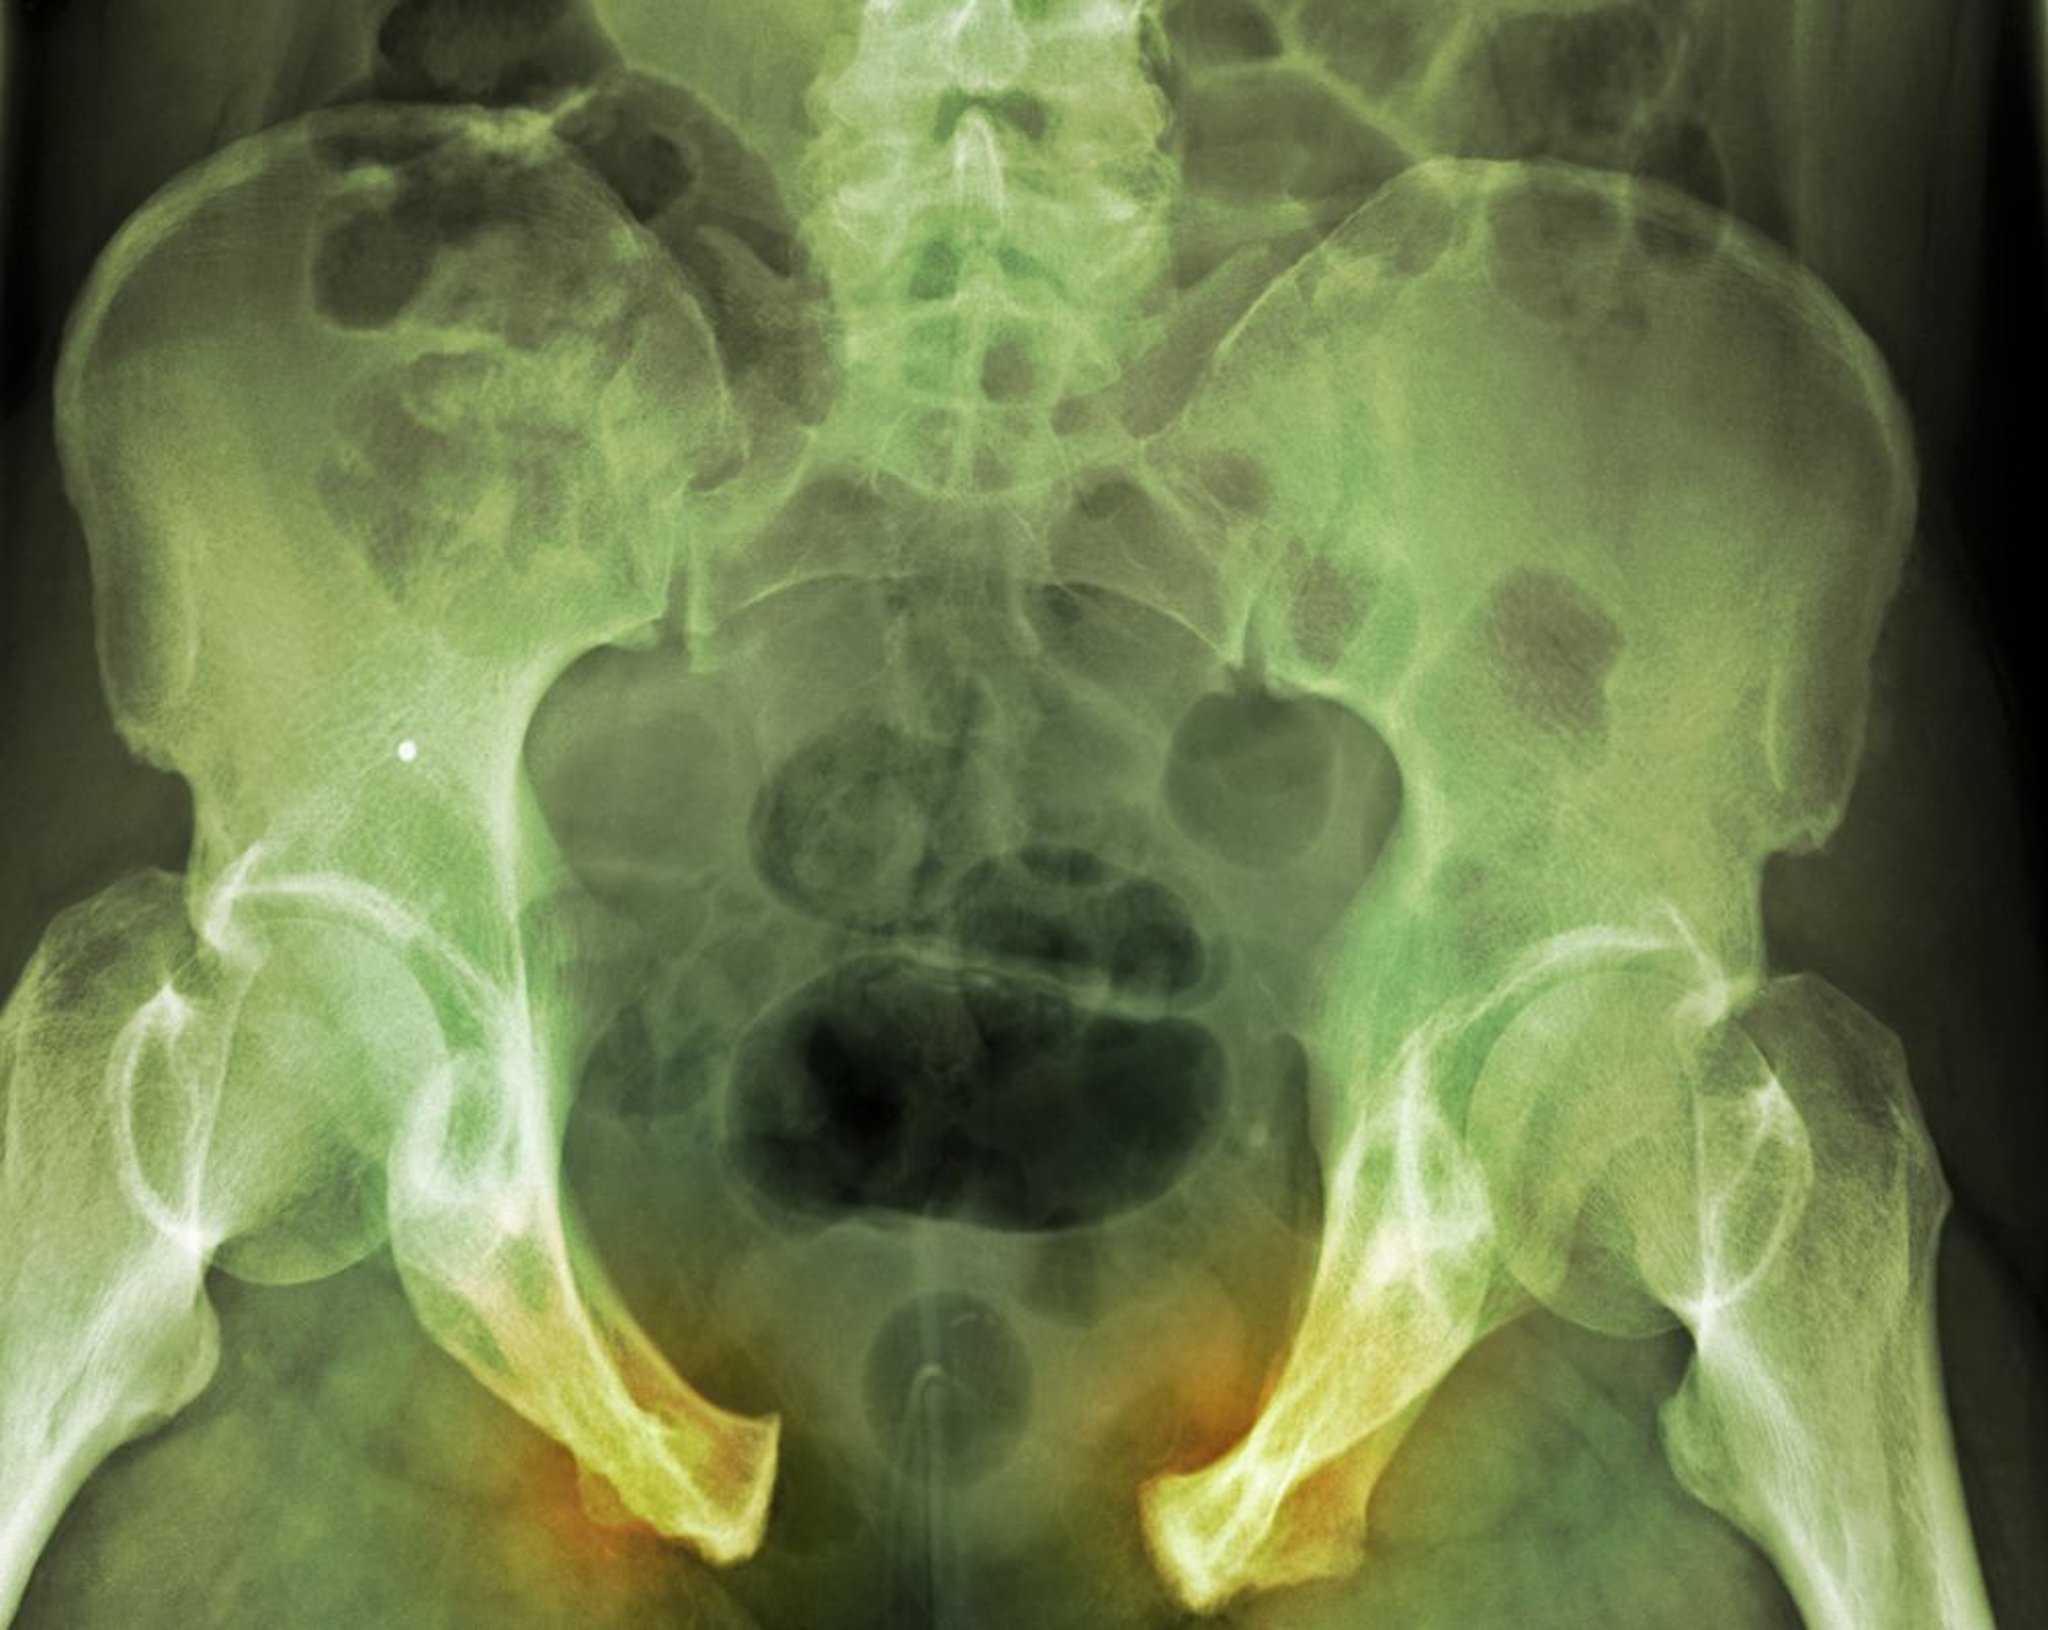

Fractura de la pelvis

En esta lesión grave, la rotura del anillo pélvico se evidencia con claridad a través de una separación amplia de la sindesmosis del hueso púbico y los ligamentos sacroilíacos del lado derecho. Las líneas de fractura no son tan evidentes.

DU CANE MEDICAL IMAGING LTD/SCIENCE PHOTO LIBRARY